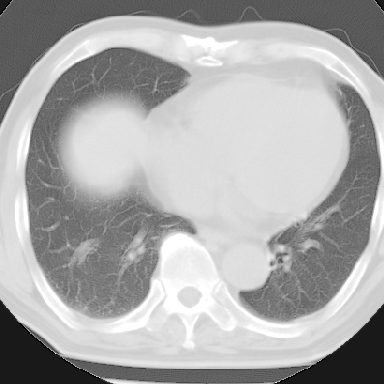

标题: CT8275:M 77 反复咳嗽咳痰10多年,慢性支气管炎请分析 [打印本页]

标题: CT8275:M 77 反复咳嗽咳痰10多年,慢性支气管炎请分析

m 77 反复咳嗽咳痰10多年,再发加重4天